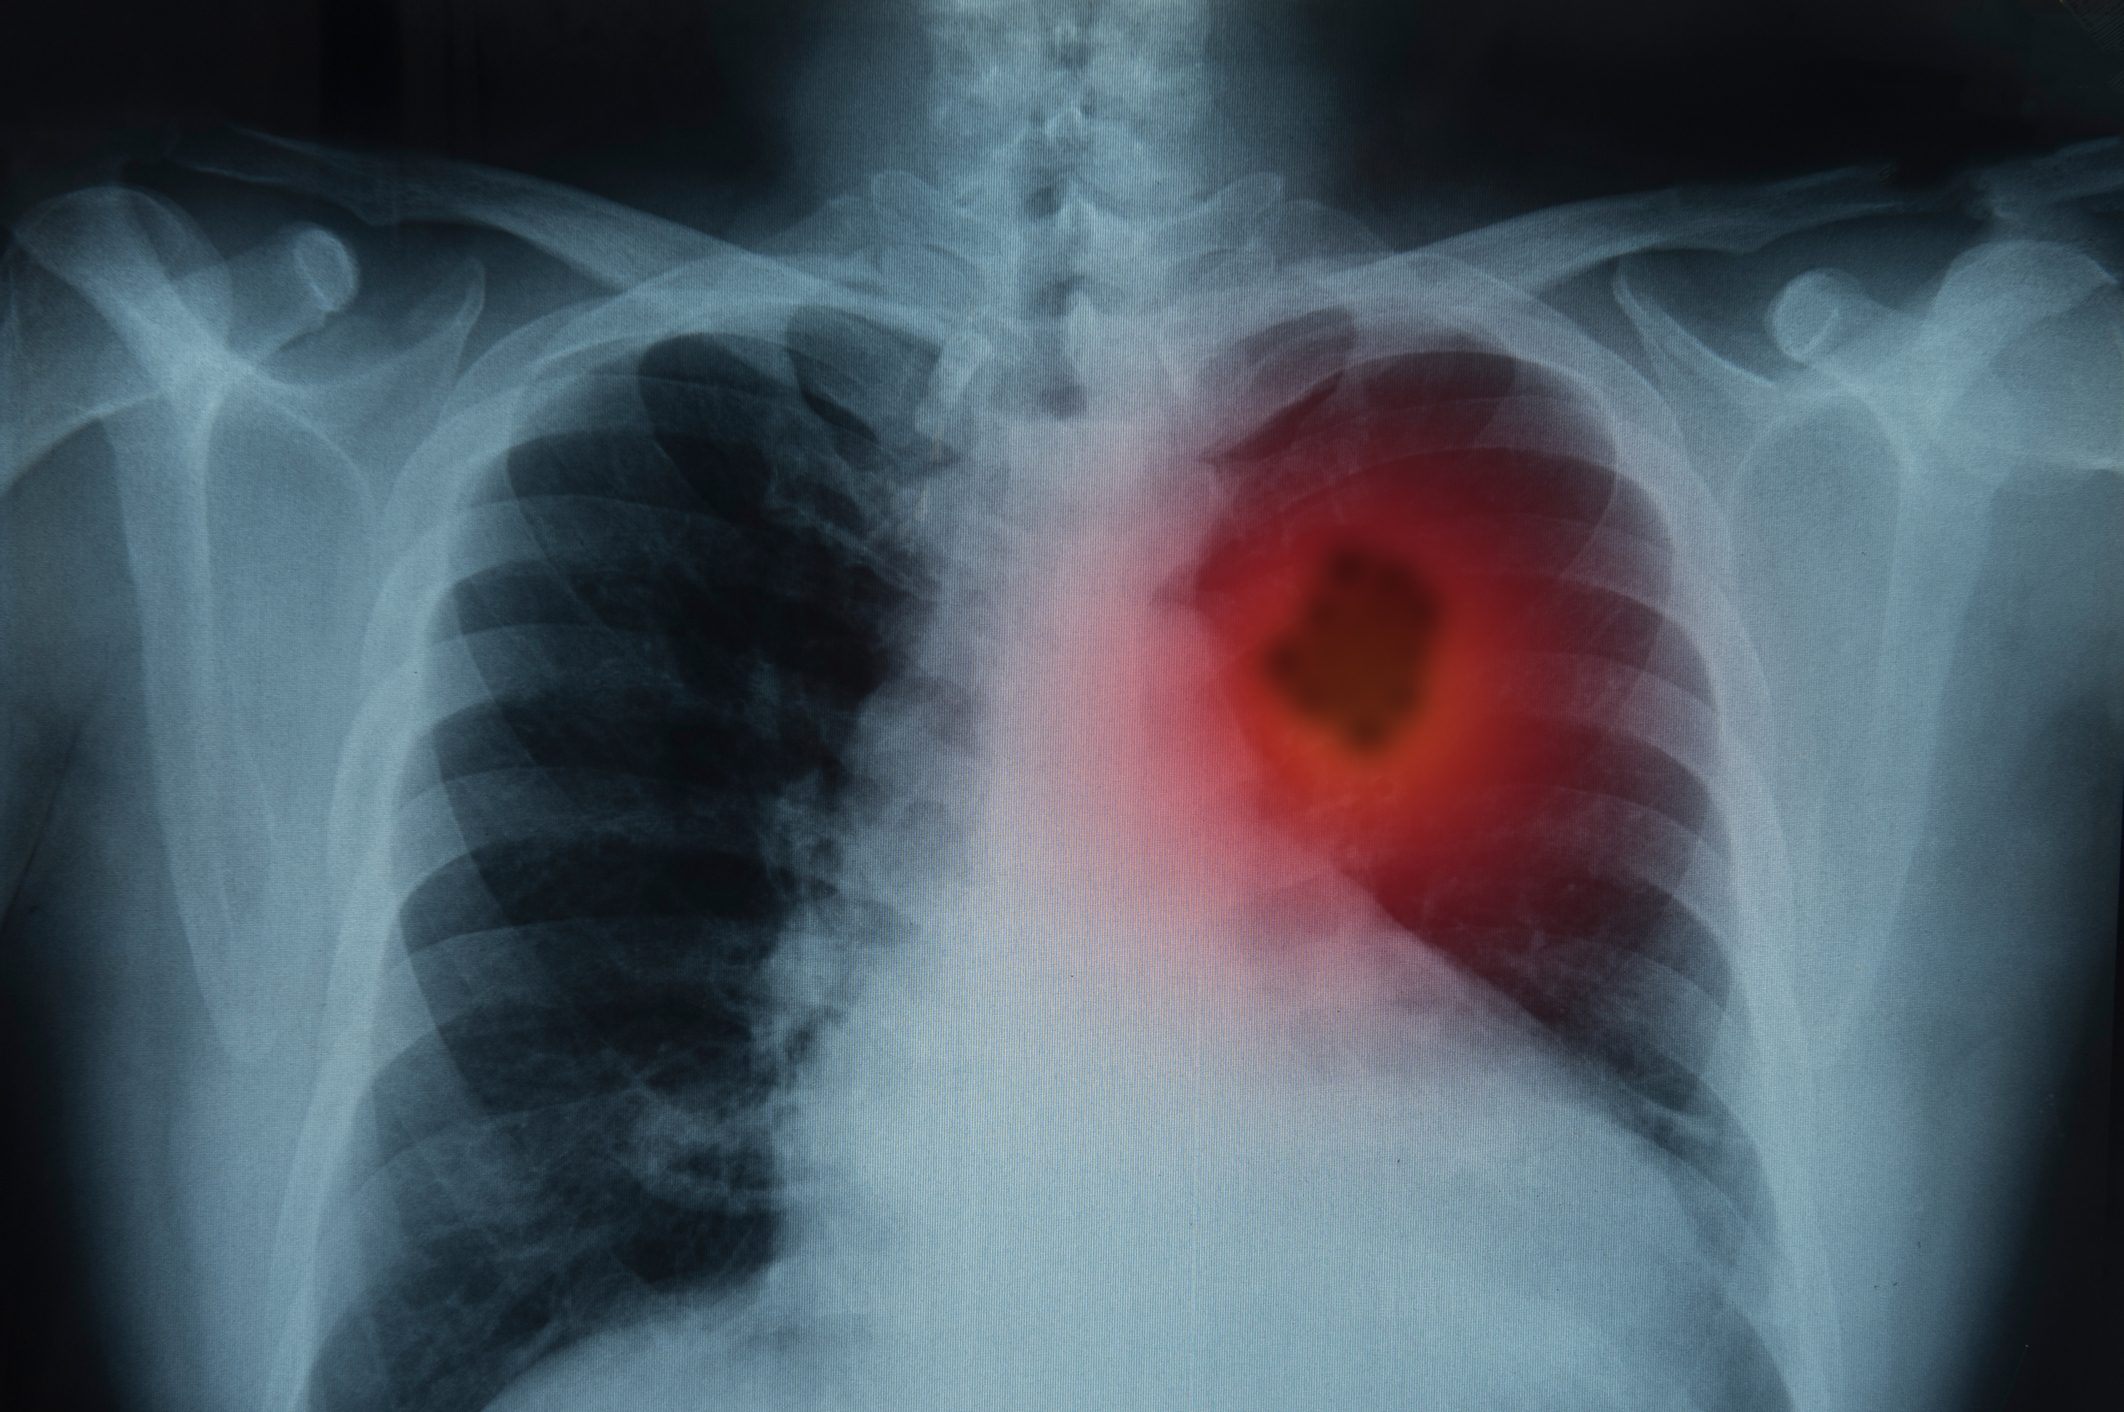

Acesta a declarat că nicotina, la fel ca în țigările obișnuite, este probabil să provoace aceste efecte asupra sănătății. Nicotina, prezentă în tutun și în țigările electronice, inflamează țesuturile și poate provoca daune. Utilizarea pe termen lung a nicotinei poate crește riscul de boli de inimă.

Nicotina îngustează, de asemenea, vasele de sânge ale gingiilor, gâtului și plămânilor, limitând fluxul sanguin al țesuturilor. Okano spune că acest lucru poate împiedica vindecarea după o intervenție chirurgicală orală sau o leziune a gurii.

Unele cartușe de vape conțin diacetil, o aromă artificială de unt. Efectele asupra sănătății ale concentrațiilor scăzute de vapori de diacetil sunt necunoscute. Inhalarea unor niveluri excesive de diacetil poate produce cicatrici pulmonare care limitează fluxul de aer, provocând epuizare, respirație șuierătoare și deces.